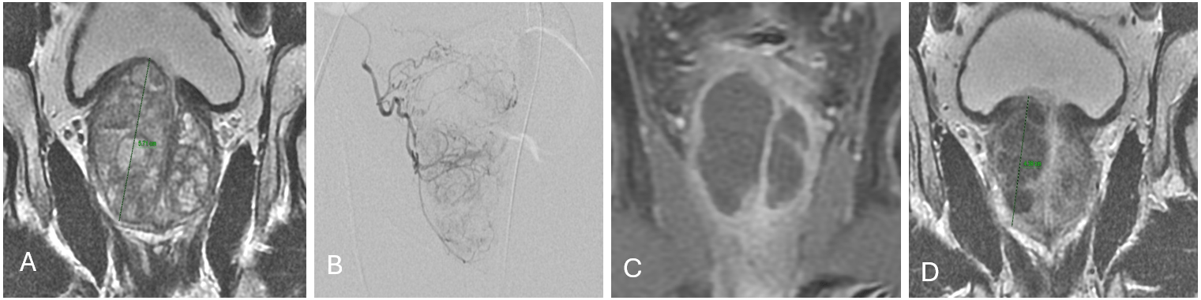

Figure 1. Typical course of prostate artery embolization (PAE). A. The pre-interventional planning MRI (coronal T2w) shows right-dominant and adenoma-dominant hyperplasia of the prostate. B. Typical contrast enhancement of the right prostate lobe in angiography. C. Complete devascularisation of both prostate lobes just two days after PAE (coronal T1-weighted MRI). D. Measurable shrinkage of the prostate after just two months; the coronal cranio-caudal diameter of the prostate is reduced from 5.7 cm before therapy to 4.3 cm. The reduced perfusion of the prostate persists.